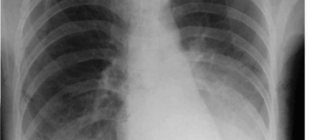

- неяркие проявления на рентгенограмме;

Нередко изменения на рентгенограммах предшествуют клинической симптоматике. А при выраженом иммунодефиците требуется выполнение более чувствительного метода компьютерной томографии для диагностики совсем небольших очагов.

Диагноз ставится на основании комплексного обследования. На рентгеновском снимке четко просматривается интерстициальная или мелкоочаговая инфильтрация легких. Обязательно назначается анализ на выявление иммуноглобулинов к возбудителям. Схема лечения разрабатывается индивидуально для каждого пациента.

Симптоматика такой пневмонии напоминает ОРВИ, затем присоединяются одышка и боль в груди, кожная сыпь, носовые кровотечения. На рентгеновском снимке выявляют участки инфильтрации в виде размытых пятен и теней. Выявить возбудителя можно по результатам анализа мокроты, мазков из носа и горла больного. Лечение включает симптоматические средства и специфические препараты. При условии правильно подобранной терапии, выздоровление наступает в течение 2 недель.

Аускультативно в легких преобладают влажные хрипы, на рентгенограммах прослеживаются долевые очаги инфильтрации с тенденцией к слиянию, плеврит.

- рентгенография легких в нескольких проекциях;

- компьютерная томография;